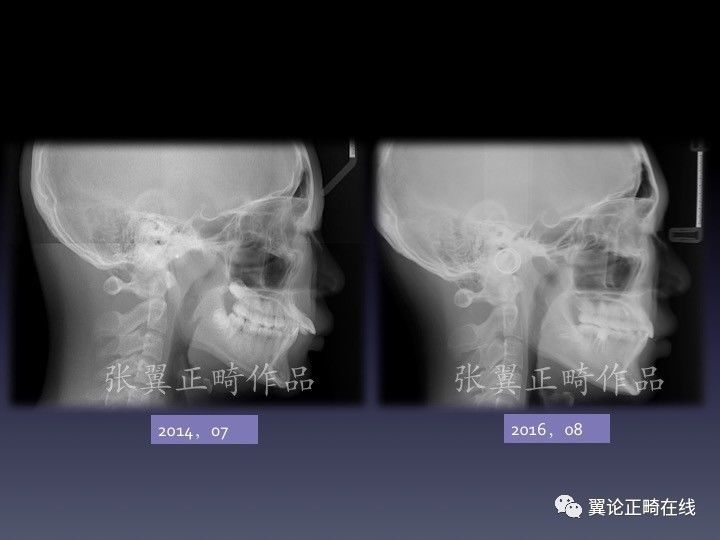

病例展示